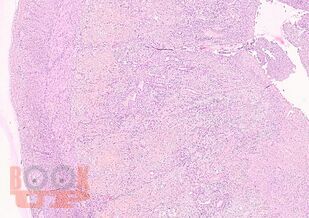

Учебное пособие разработано по дисциплине «Патологическая анатомия - патологическая анатомия головы и шеи» в соответствии с Федеральным государственным образовательным стандартом высшего профессионального образования для студентов, обучающихся по основным образовательным программам высшего образования - программам специалитета по специальности «Стоматология».

В учебном пособии представлен теоретический материал, перечень макропрепаратов и микропрепаратов, демонстрирующих типовые проявления патологических процессов. В цветных иллюстрациях и в описании микропрепаратов сделан акцент на наиболее важных гистологических изменениях, позволяющих на светооптическом уровне диагностировать и дифференцировать состояния, отклоняющиеся от нормы, в том числе с использованием различных гистологических окрасок. Пособие помогает выделить главные аспекты изучаемых патологических процессов, организовать и конкретизировать учебный процесс.